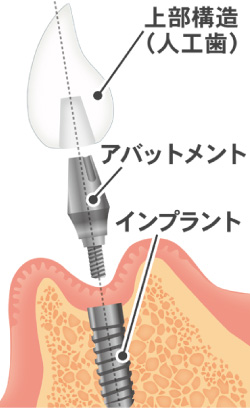

インプラント治療とは術前診査・診断を十分に行った上で、歯が抜けてしまった部分にインプラント(人工歯根)を埋め込み、その上から自然な見た目の人工歯を装着させるという治療法で、骨にしっかりとインプラント(人工歯)を定着させるため、自分の歯のようにしっかり、思い切り噛めるようになります。